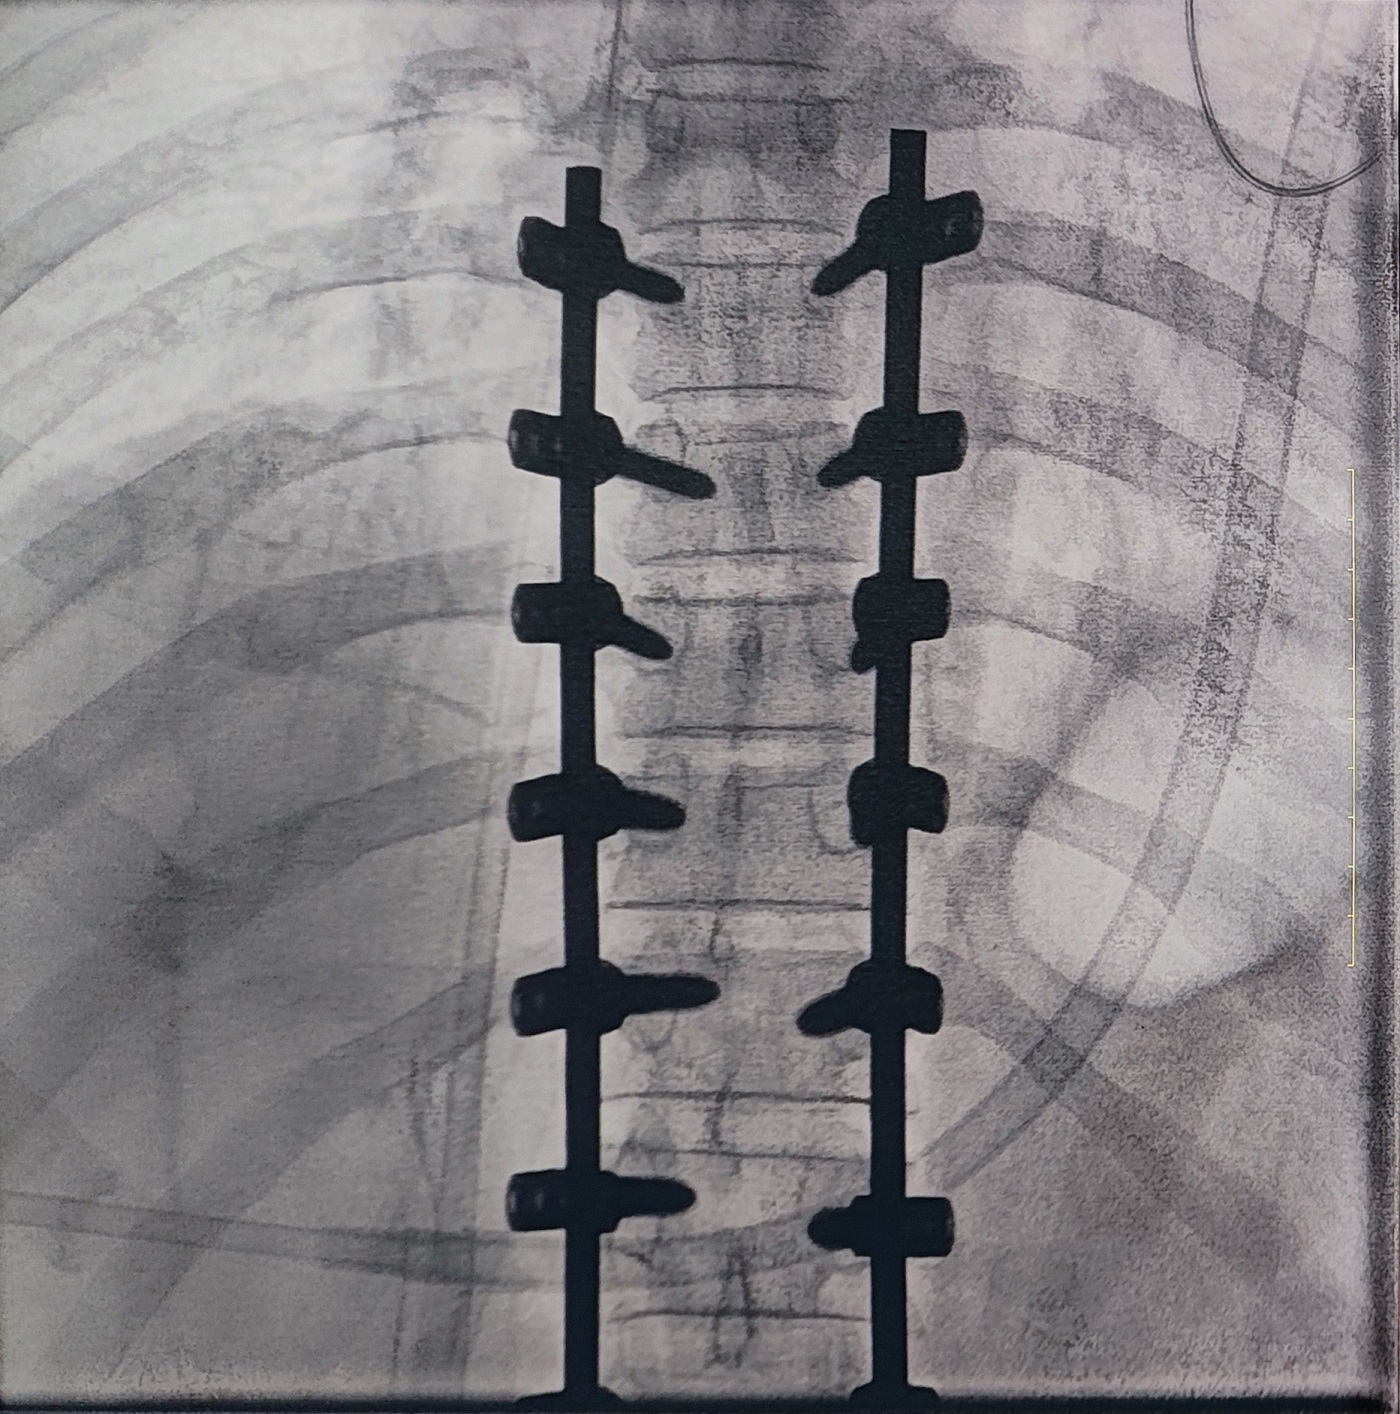

一場(chǎng)脊柱手術(shù)中,醫(yī)生需要拍攝跨越7個(gè)節(jié)段的脊柱影像,由于曝光的視野較大,常規(guī)視野的C形臂通常需要拍攝2-3次,普愛(ài)醫(yī)療大平板一體式C形臂30CM*30CM的“大視野”,輔助醫(yī)生一次性完成了7個(gè)節(jié)段的拍攝。最終,醫(yī)生在高清影像的輔助下完成了14枚螺釘?shù)木珳?zhǔn)定位、置入。

大視野,不僅意味著醫(yī)生可以更快,獲取更全面的影像信息,做出精準(zhǔn)判斷,無(wú)需多次拍攝定位,也顯著地降低了患者接受的輻射劑量。